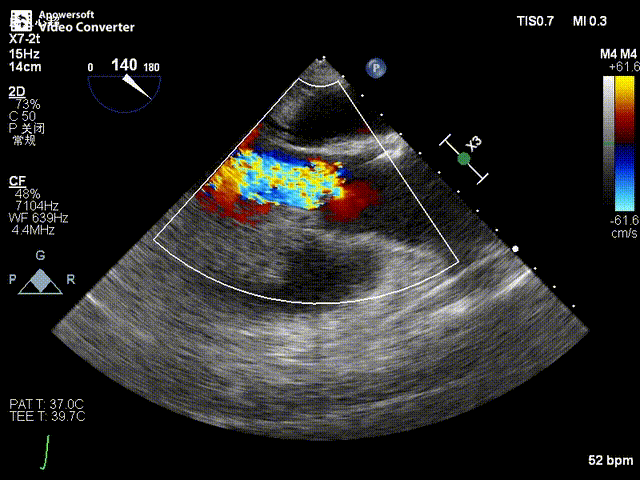

术前超声影像图

患者为84岁女性,因“主动脉瓣重度关闭不全”收治入院。入院诊断:主动脉瓣重度关闭不全,心功能IV级;冠状动脉粥样硬化性心脏病。心脏超声提示“主动脉瓣重度关闭不全;瓣口水平以下左室下壁、后下壁搏幅减低;左房、左室大、右房大小正常高限;主动脉硬化;左室收缩功能减低”。经张海波教授团队综合评估,患者属于外科手术高危人群。

患者全麻后,于左侧心尖3-4cm处进行微创手术切口。在DSA及超声引导下,输送Ken-Valve瓣膜系统进入左心室,边调弯边推送,使得瓣膜在术中始终保持较好的同轴性,从送入输送器到瓣膜释放不足十分钟。术后即刻患者反流消失,于外科杂交手术室拔除气管插管,次日即由ICU转入普通病房。